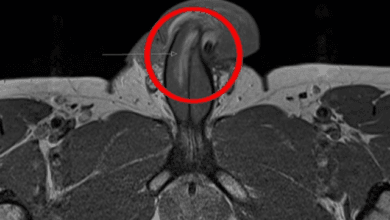

Más de 20 amputaciones de pene en tres años se han realizado en Lara por VPH

Está hospitalizado y en los próximos días ingresará a pabellón del Hospital Central Antonio María Pineda. Nervios e incertidumbre, frente…